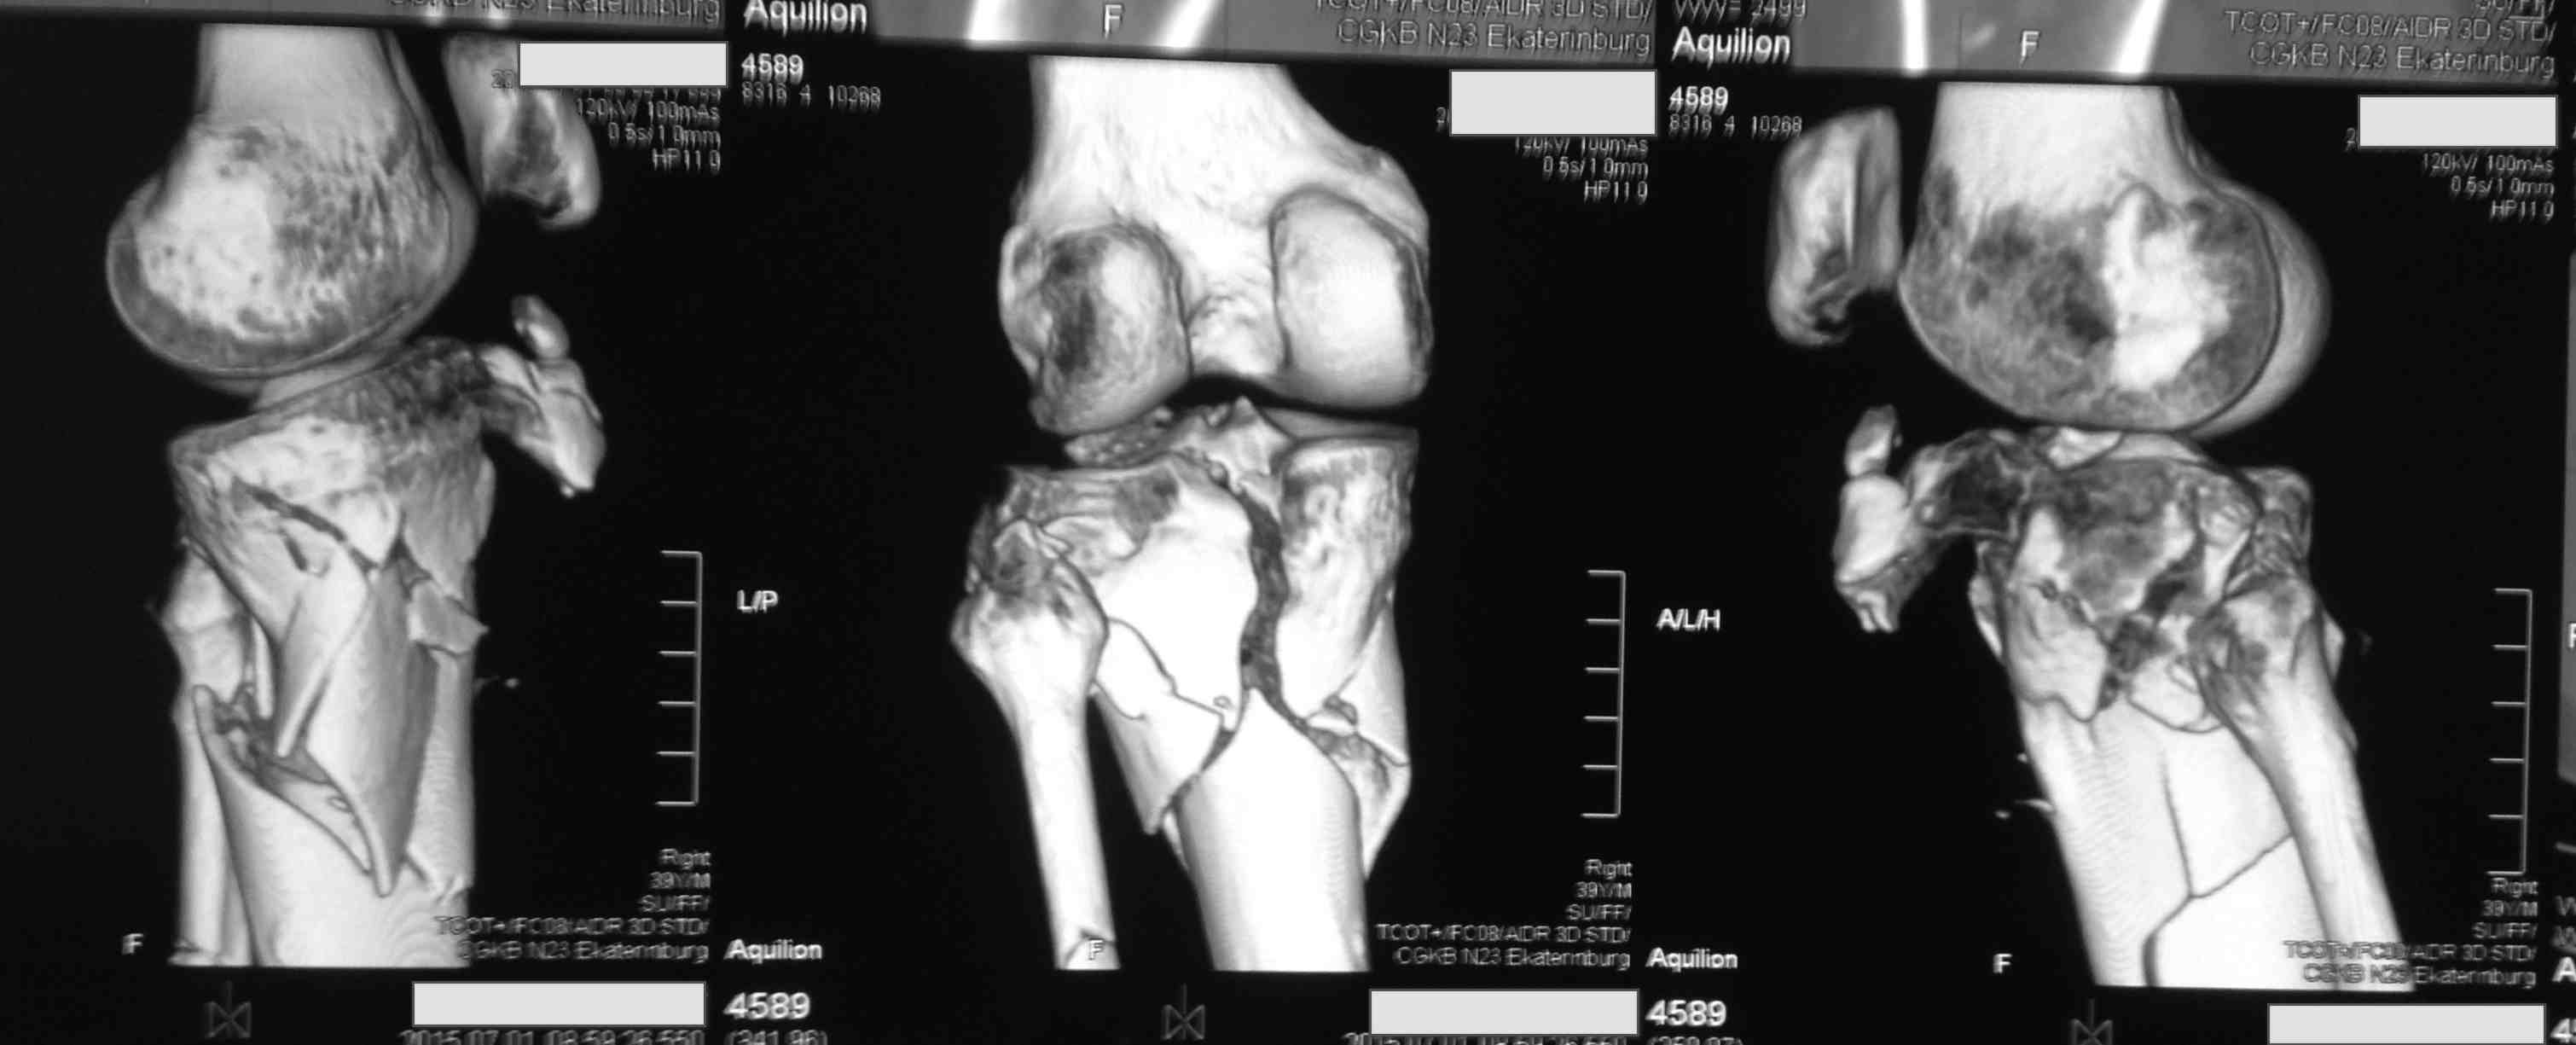

Серия КТ сканов в аппарате

Голень-41-С3.1 - полный внутрисуставной и метафизарный оскольчатый перелом с доминантным повреждением наружного мыщелка, с импрессией центральной части плато. Первичная тактика полный респект по АО и ОТА. на фоне лигаметотаксиса выполнено КТ, которое четко детализирует повреждение и определяет дальнейшую тактику.

Основная проблема не бугристость, а внутрисуставное повреждение латерального мыщелка с импрессией центральной части. С большей вероятностью, есть паракапсуллярное продольное повреждение наружного мениска.